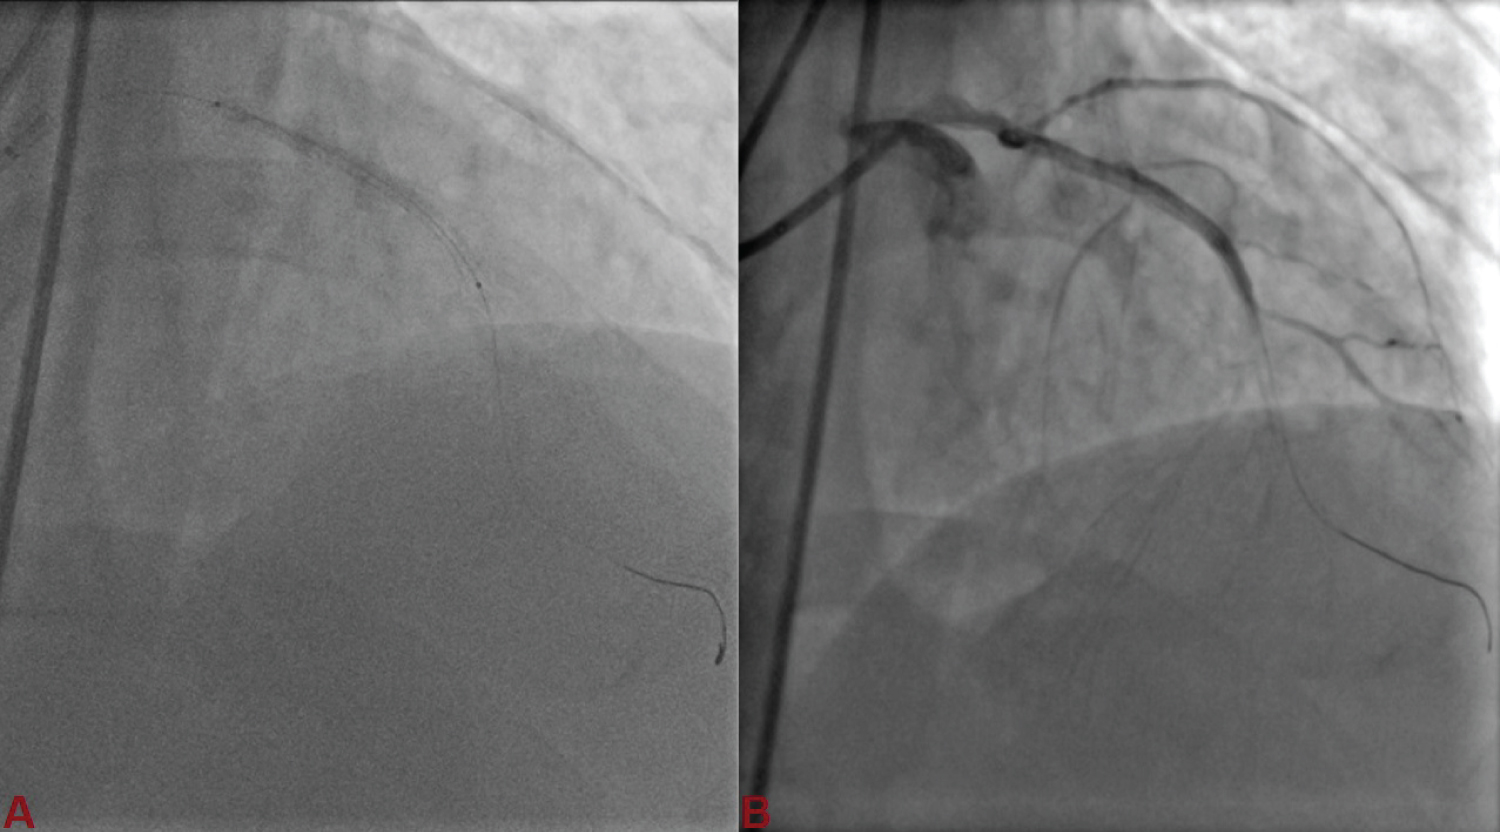

A 76-year-old male, smoker and hypertensive presented with chronic stable angina- Canadian Cardiovascular Society (CCS) class III. Coronary angiography was performed after proper consent which revealed diffuse disease of proximal left anterior descending artery (LAD) with significant stenosis. Aortic sinus was little dilated, so little difficulty was encountered in cannulating left main with Judkins left (JL) guiding catheter. Lesion was wired with runthrough (Terumo, Japan) and sequentially dilated with 1.5 × 10 and 2 × 10 mm Sapphire semicompliant balloon (Orbus Neisch, Netherland) (Figure 1A). After balloon dilatation, dissection at the distal edge was noticed (Figure 1B). As stent could not be tracked and pushed along the lesion as guide catheter used to back out, it was decided disease to change the guide catheter to extra backup (EBU) guide catheter. We could not pass the wire across the lesion and park it distally. Patient started complaining of chest pain. On contrast injection, our wire was seen into the false lumen along with a long segment spiral dissection spreading downward (Figure 2A) and the left circumflex artery was not visible (Figure 2B). It was inferred that spiral dissection was spreading bi-directionally. Keeping runthrough wire there, Sion black (Ashahi, Japan) was tried to be parked into true lumen using parallel wire technique. Once Sion wire was in true lumen distally, runthrough wire was pulled out. It was decided to seal the dissection first. 2.75 × 38 mm Xience Prime everolimus eluting stent (Abott Vasc, USA) was deployed at 12 atm pressure to seal the flap (Figure 3A and Figure 3B). LCx was carefully wired using Sion wire, and dilated with 1.5 × 10 mm Sapphire balloon restoring the flow (Figure 4A). It was stented with 2.75 × 23 mm Xience Prime stent at 12 atm pressure, thereby sealing the dissection and restoring LCx (Figure 4B and Figure 4C). Sion wire in LAD was carefully manuvoured and parked distally into true lumen (Figure 5A, Figure 5B and Figure 5C). The dissection flap was still visible starting from the distal edge of the deployed stent. Another 2.5 × 28 mm Xience Prime stent was deployed overlapping with proximal stent (Figure 6A). The Stent was post dilated by 2.75 × 10 mm Sapphire non-compliant (NC) balloon. Both the LAD and LCx started showing TIMI III flow after stenting with complete sealing of dissection flap (Figure 6B). He was discharged in stable condition with prasugrel 10 mg, aspirin-75 mg, rosuvastatin- 40 mg, metoprolol-100 mg, and ramipril-10 mg.

Figure 2: A) Wire was seen into the false lumen along with a long segment spiral dissection (red arrowhead) spreading downward; B) The left circumflex artery (arrow) was not visible. View Figure 2